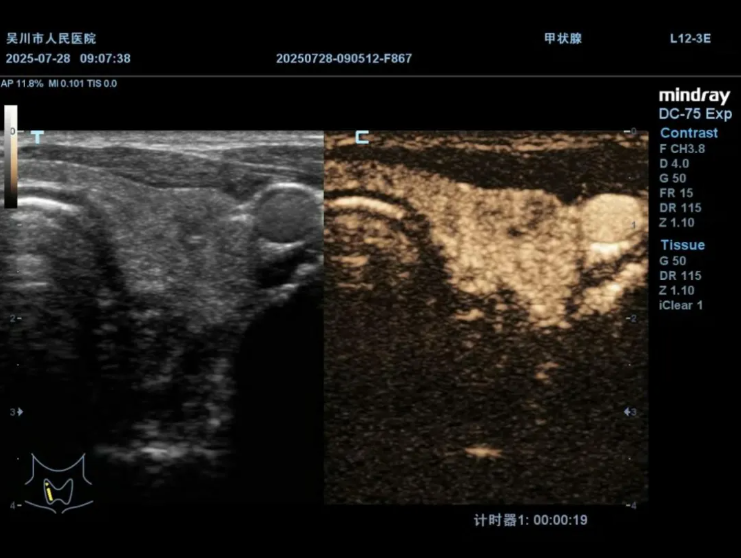

术前造影,明确结节内部情况与周围组织关系

术后超声造影

明确消融范围覆盖结节,确保消融效果